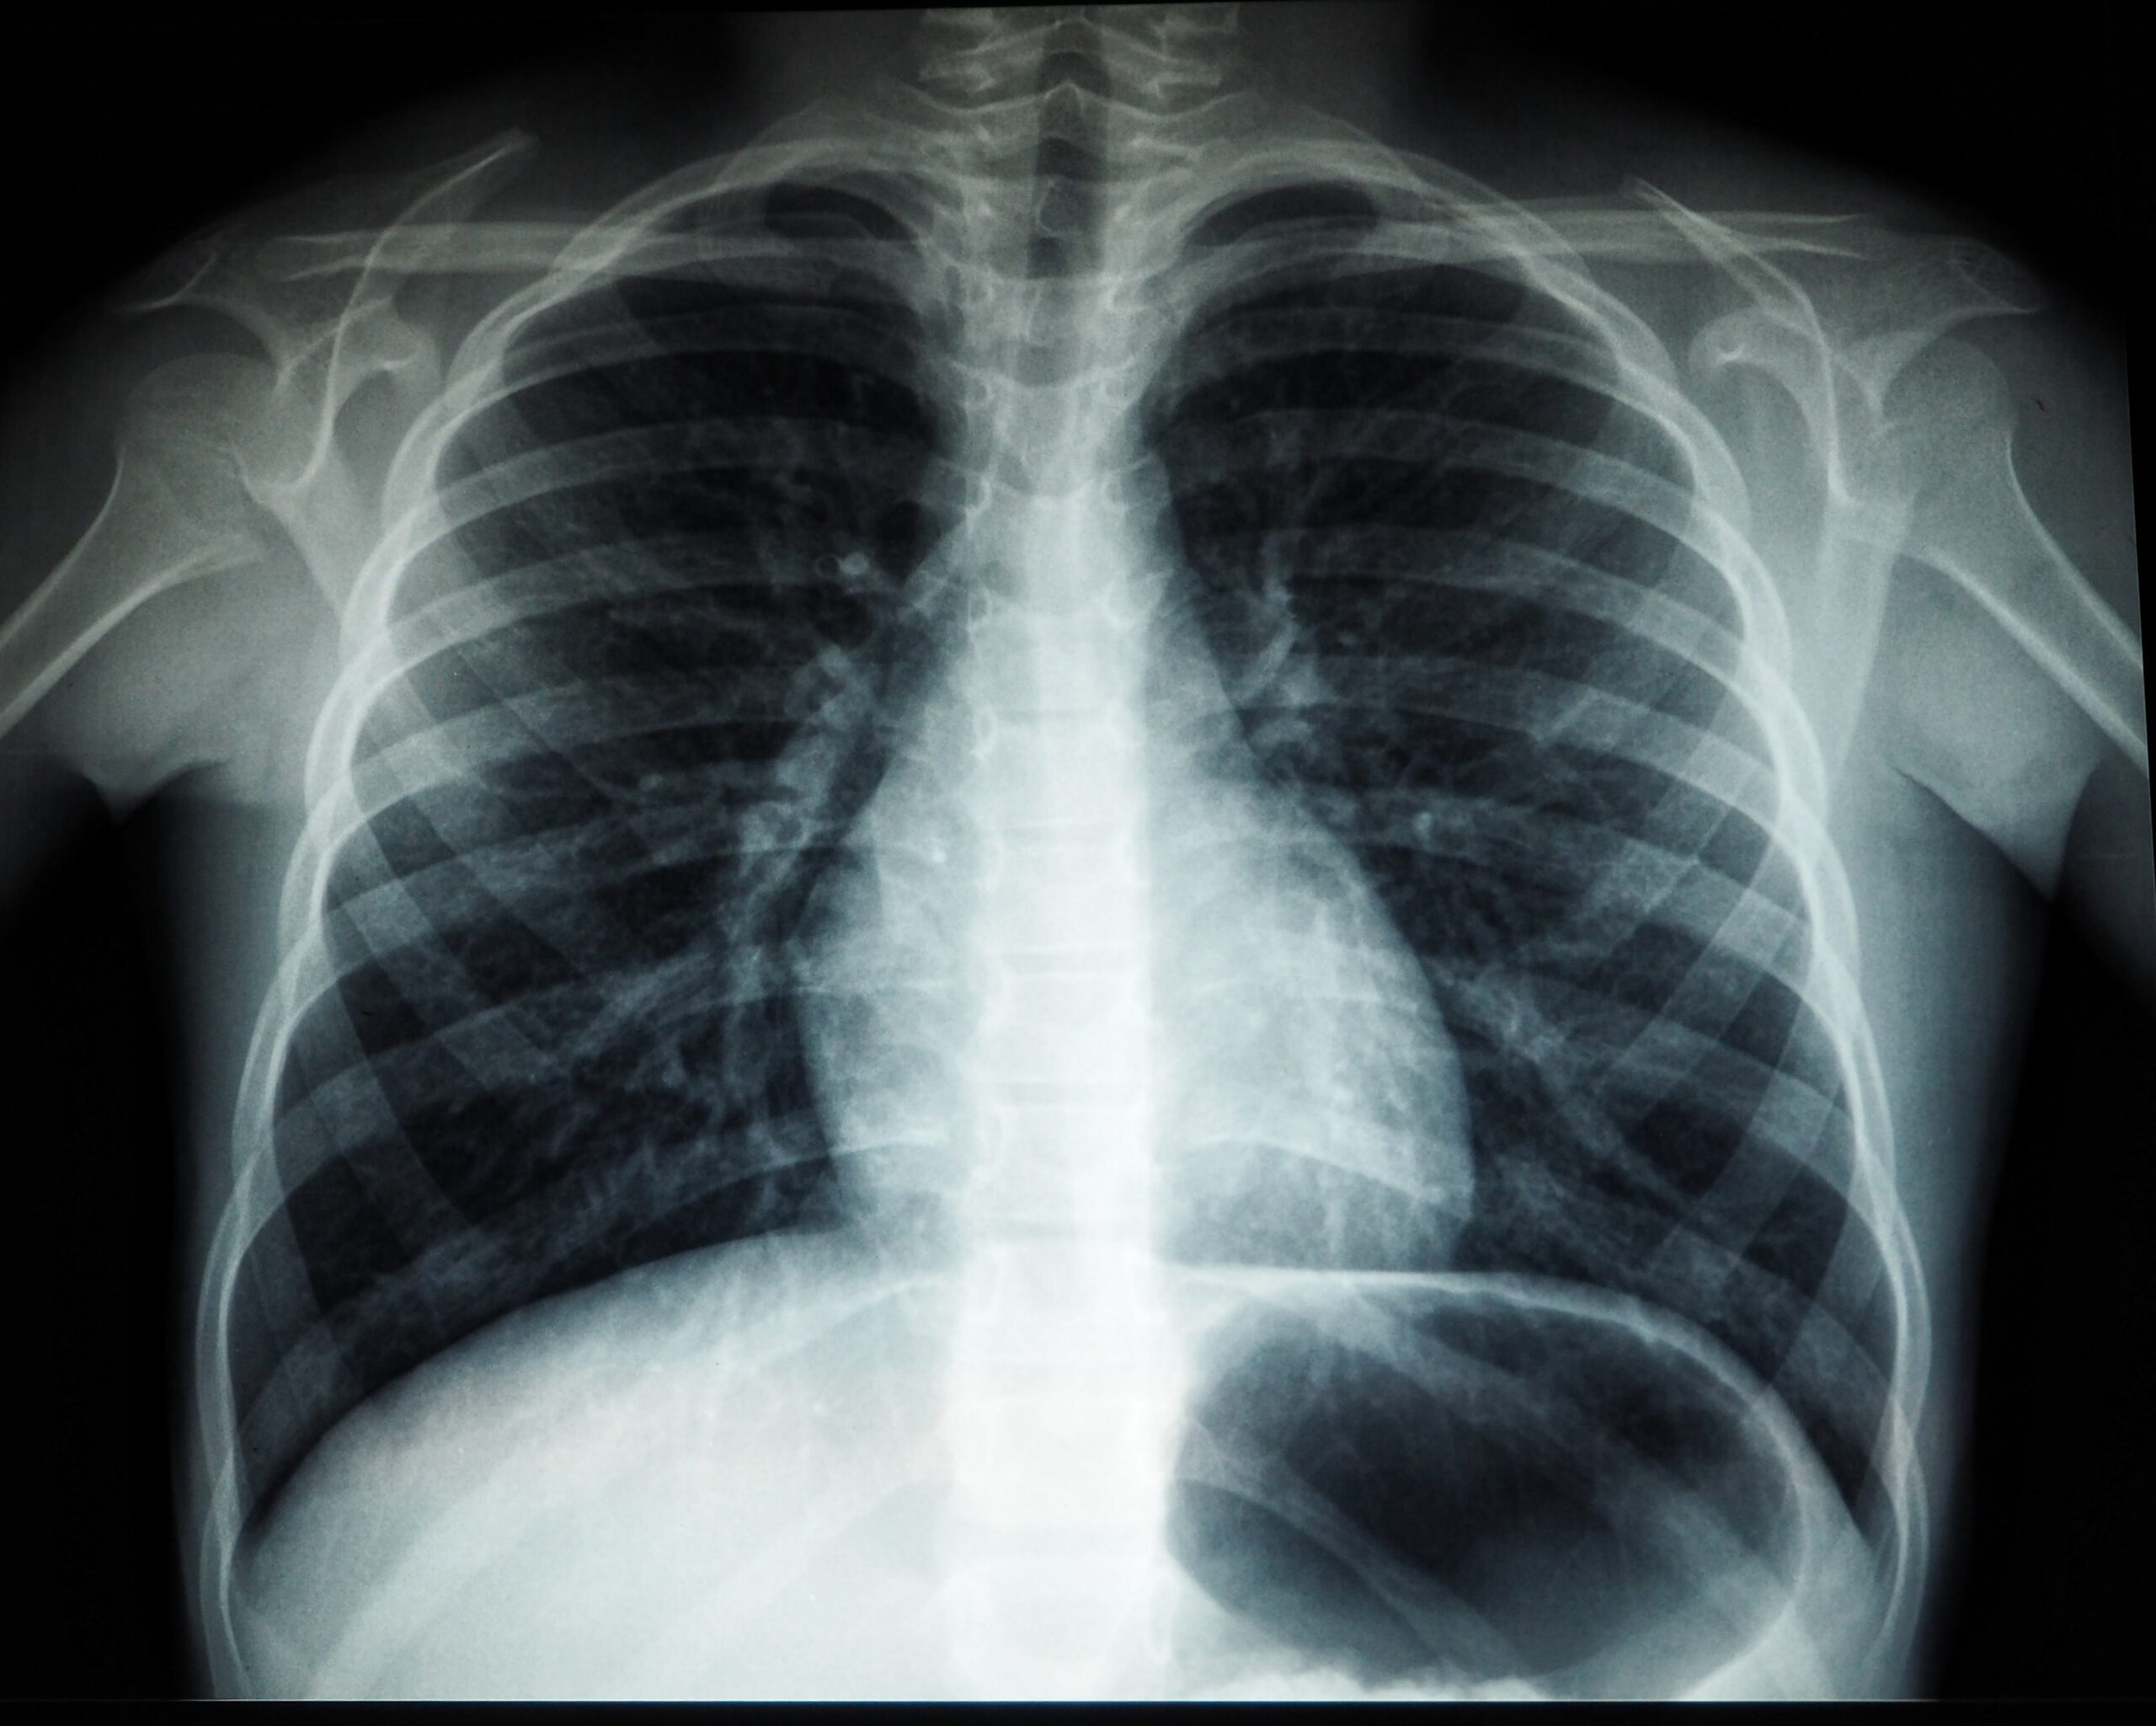

Digital radiography is a form of radiography that uses x-ray–sensitive plates to directly capture data during the patient examination, immediately transferring it to a computer system without the use of an intermediate cassette. Ashmed Specialist Hospital installed the latest technologies for digital X-Ray imaging to support the diagnosis process for physicians in several specialties including Obstetrics, Internal Medicines, Oncology, Gynecology, Orthopedics, Pediatrics, Urology and Cardiology.